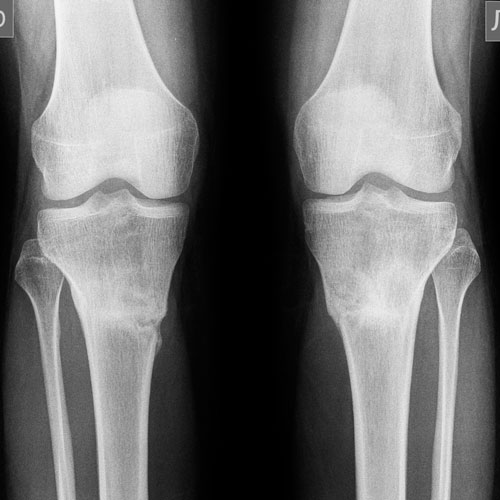

Дата операции 11.03.2014г.

Дата снятия аппаратов 10.06.2014г.

Срок лечения 3 месяца.

Почти 2 месяца с момента снятия аппаратов.